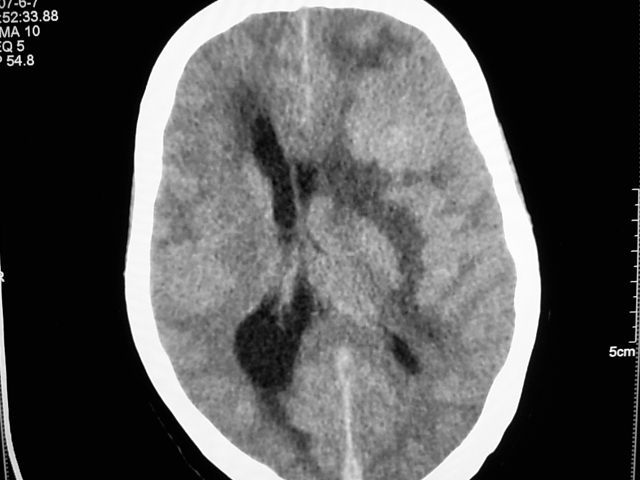

患者 女 63岁,近几周感觉头部不适来查体。

请调骨窗。多考虑前中颅窝脑外肿瘤,脑膜瘤、淋巴瘤或血管外皮瘤均有可能,蝶嵴脑膜瘤可能性最大。

左侧额颞部巨大肿块,平扫呈略高密度,增强明显强化,周围水肿明显,左侧侧脑室受压,右侧侧脑室扩大,中线明显右移,局部骨质增厚,支持脑膜瘤、大脑廉下疝。